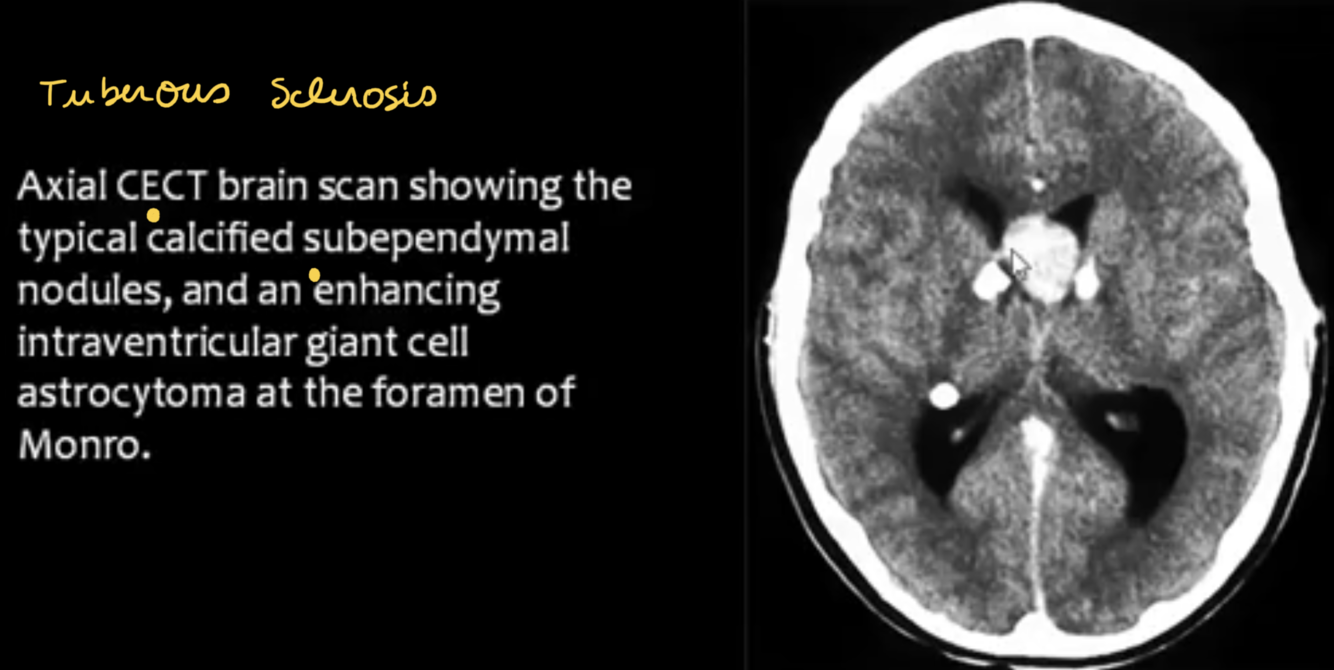

TECTAL GLIOMAS

major points